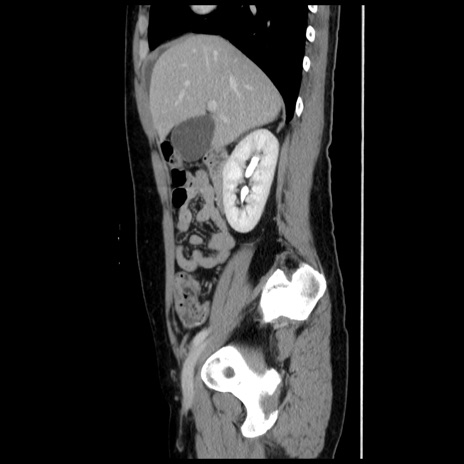

横断像

【症例】 50歳代女性

【主訴】 腹痛

【現病歴】前日生レバーを食べた。今朝に排便あり。 昼前に突然発症の腹痛を生じ、当院救急外来を受診した。

【既往歴】 子宮筋腫にてで子宮全摘後

【身体所見】 意識清明、腹部:平坦、軟、下腹部やや左を中心に圧痛・反跳痛あり、筋性防御あり

【データ】WBC 7800、CRP 0.07